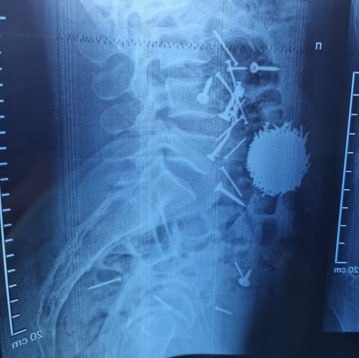

Vaib.uz (Узбекистан. 6 января). Необычную историю спасения рассказали в Самаркандском филиале Республиканского научного центра экстренной медицинской помощи. На днях в приёмное отделение был доставлен 29-летний мужчина с сильными болями в области живота. После проведённой диагностики и лабораторных анализов врачи обнаружили, что в желудочно-кишечном тракте пациента находится большое количество металлических предметов – гвоздей и саморезов. Ситуация требовала немедленного вмешательства.

«Мы определили, что пациенту необходимо экстренное хирургическое вмешательство. После всех подготовительных процедур была выполнена операция методом лапаротомии и гастростомии. Из брюшной полости удалось извлечь большое количество металлических предметов – около 200 граммов. Операция длилась примерно час. Сейчас состояние пациента хорошее, он свободно передвигается», – сказал он.